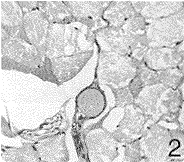

推注压力为10、20、30、40 kPa时,微球栓塞血管直径分别为185、108、68和67 μm,而血管离肿瘤组织最近距离分别为682、532、264和235 μm。推注压力为10~20 kPa时,微球主要栓塞于肌性小动脉水平,微球不能完全栓塞血管腔,离肿瘤组织较远(图1)。当其为30~40 kPa时,栓塞至微动脉水平,微球栓塞血管腔完全,充分阻断血流,离肿瘤组织较近(图2)。推注压力为30 kPa时,已经完全栓塞微动脉,故最佳灌注压力为30 kPa(表1)。

图 2 18周组,灌注压力为30KPa时,微球栓塞至壁厚约3μm仅有1层完整平滑肌的微动脉水平,微球栓塞血管腔完全,离肿瘤组织较近 HE×40